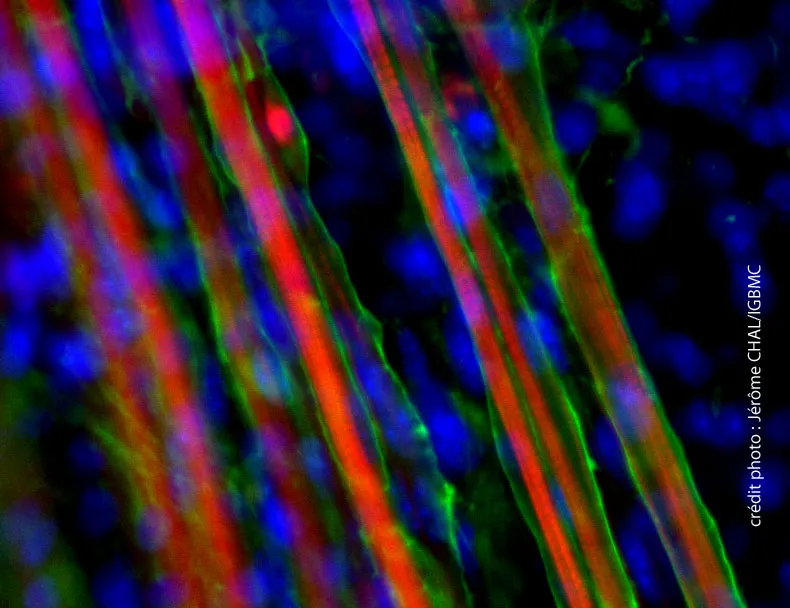

Sarepta Therapeutics, dans un communiqué de presse daté du 1er octobre 2015, communique des résultats additionnels concernant l’évaluation de l’eteplirsen (oligonucléotide antisens visant le saut de l’exon 51 du gène DMD) dans la dystrophie musculaire de Duchenne.